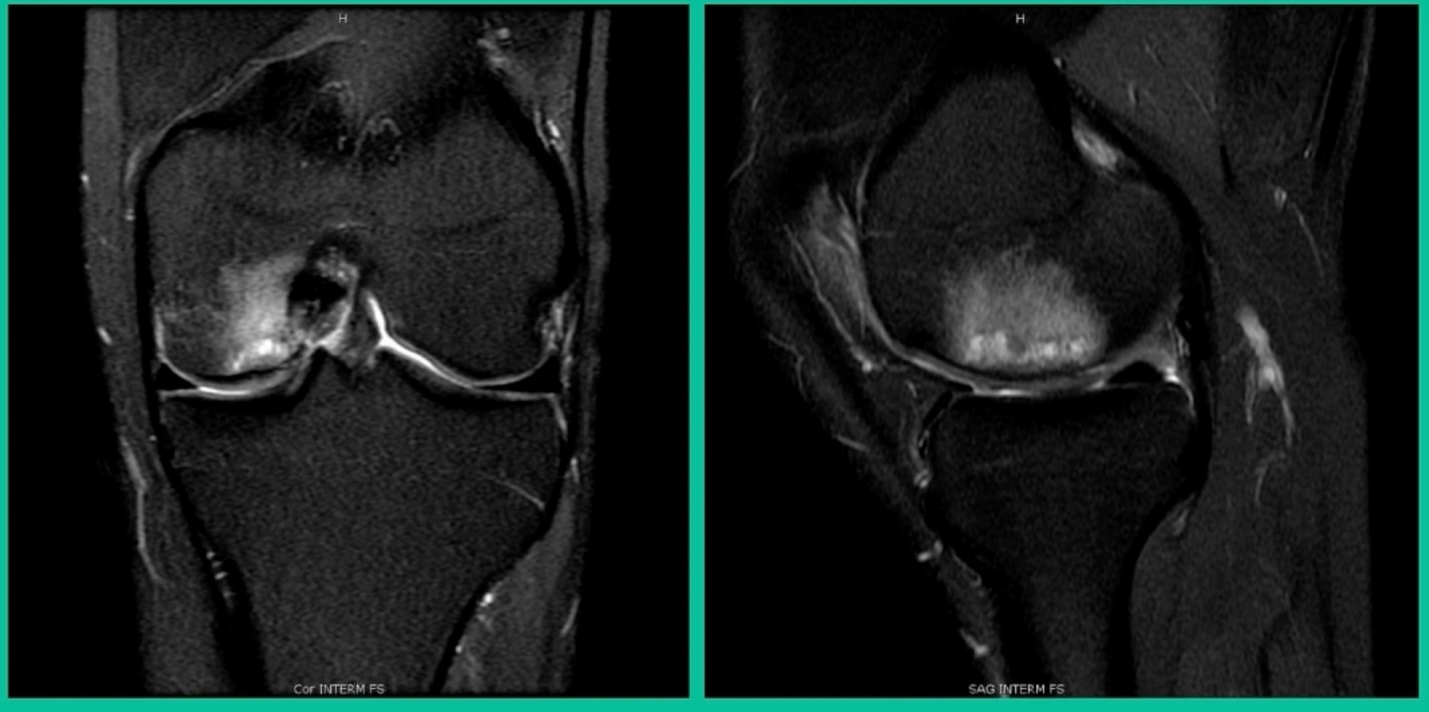

43-Year-Old, symptomatic medial femoral condyle.

D1 football player formally, affecting ADLs. For this one, I initially just wanted to watch it. This looks pretty small when he came in. Let’s see what happens. Six months later, this is where he progressed to.

We get in there, it’s delaminated, not much bone, nothing to fix in my mind, and so we drilled it.

How do these do? There’s actually reasonable data for marrow stimulation for OCD. But if you have the option for small defects, I would prefer an osteochondral allograft over microfracture based on the literature. That’s the take-home. Marrow stimulation, if you do it, you’re probably better off drilling it. We showed that we could reduce revision rates with marrow stimulation by two-thirds if you drill it versus use a microfracture awl.